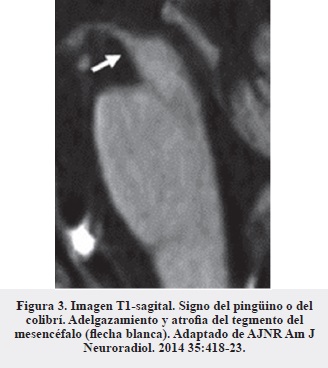

En nuestro caso la realización de la resonancia de cerebro constituyó una herramienta muy útil que, además de argumentar la sospecha clínica inicial, sirvió para descartar otras lesiones estructurales asociadas a caídas frecuentes (hematomas, hidrocefalia a presión normal, etc. ). Los hallazgos característicos de esta enfermedad son, principalmente, la atrofia del tegmento del mesencéfalo (Figura 2) en proyección sagital (signo del colibrí o del pingüino) (Figura 3) (16, 17), la alteración del diámetro anteroposterior y la atrofia generalizada del mesencéfalo (Figura 4) (18).

Un aspecto de particular utilidad de la IRM en el diagnóstico diferencial con enfermedad de Parkinson idiopática es la evaluación de la morfología de la curvatura del tegmento del mesencéfalo (Figura 5), la cual conserva su forma convexa habitual en la EP, mientras que en la PSP puede observarse recta o cóncava (18).